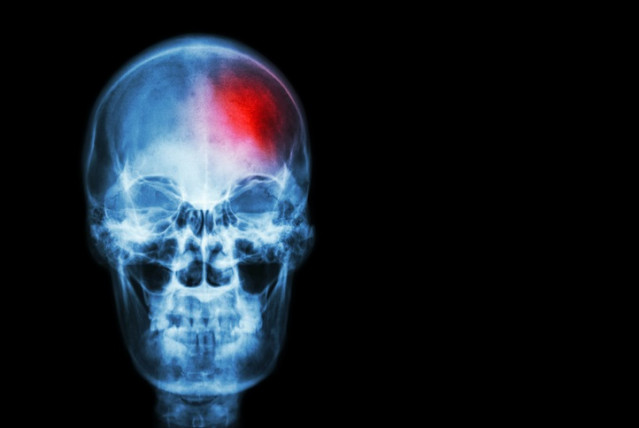

Archivo - Imagen de archivo de un ictus.